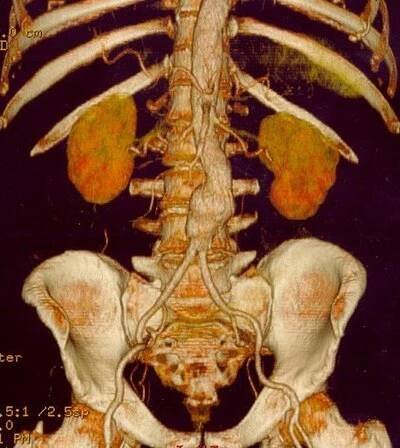

3D rekonstrukce CT skenu aneuryzmatu břišní aorty.